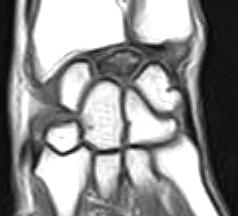

The lunate carpal bone appears hypointense on the T1 Weighted images and heterogeneously hyperintense on the GRASS images. There is slight decrease in the height of the lunate bone with slight elongation of the lunate in it's antero-posterior dimension. Fluid is noted in the region of the scaphoid and trapezium bones.

Staging and MRI Findings:

Stage I:

Conventional radiographs are usually normal in stage I However, a fracture line or compression fracture may be present. Bone scintigraphy though sensitive, is nonspecific. On MRI, it is possible to characterize the extent of necrosis and the morphology of marrow involvement and of the lunate cortical surfaces, including articular cartilage. Focal or diffuse hypointensities are seen on T1W images within the marrow. On T2W or STIR images, the lunate may show areas of increased signal intensity (hyperemia or vascular dilation). Unaffected marrow is isointense to normal marrow. Joint effusions or localized synovitis is hyperintense on T2W, GRASS or STIR images. Intravenous gadolinium with fat-suppression displays hyperemic bone with increased signal intensity.

Stage II:

Conventional radiographs show sclerosis of the lunate which corresponds to the hypointense areas on T1W images. Edema, granulation tissue and areas of preserved vascularity are hyperintense on T2W images. Usually, the morphology and size are preserved. However, a decrease in the height of the radial aspect of the lunate may be seen in late stage II disease.